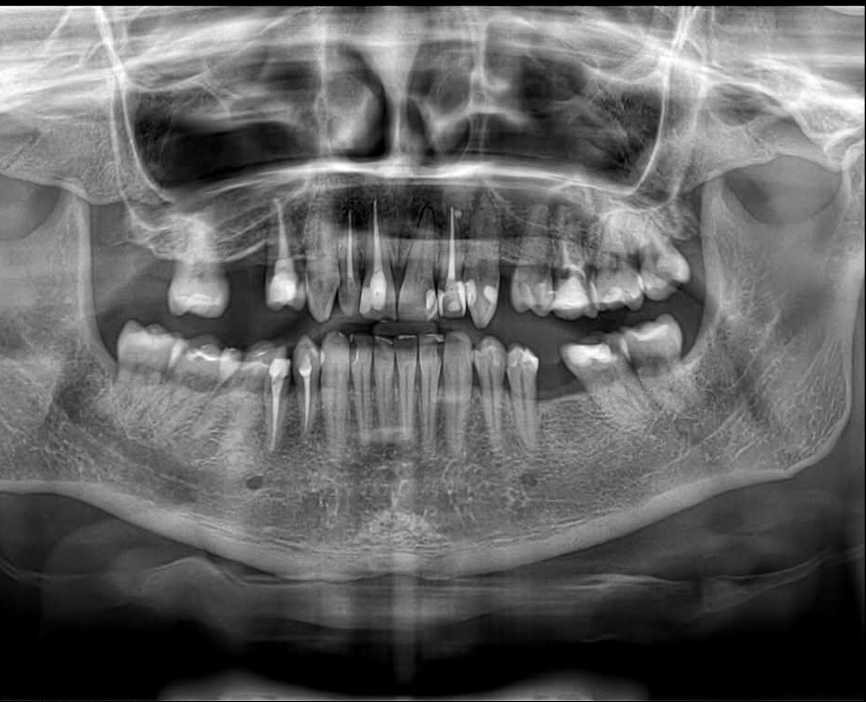

Naudojame pažangią diagnostiką ir šiuolaikines protezavimo technologijas, leidžiančias gydytojui tiksliai suplanuoti gydymą ir užtikrinti aukštą protezų prigludimo bei ilgaamžiškumo kokybę.

| Diagnostinis skenavimas | 40 € |